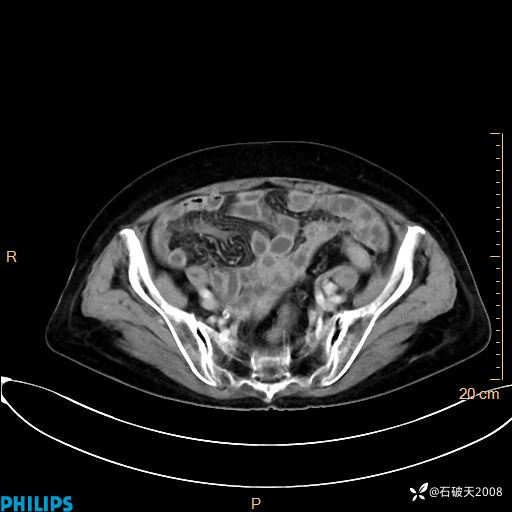

动脉期